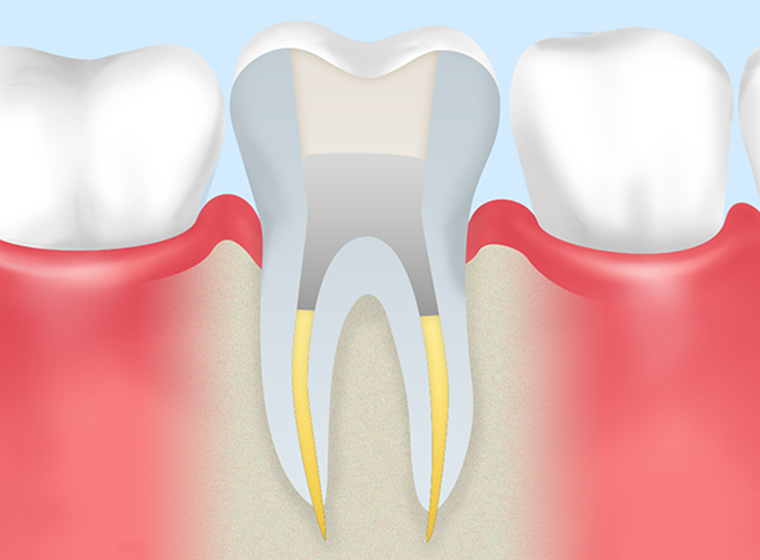

薬剤の充填 -

- STEP5

土台装着 -